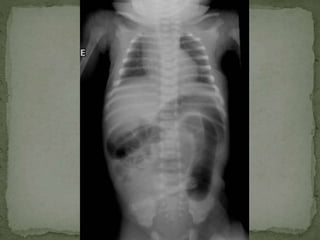

 Abdominal X ray 16th June, 2013

 Dilated bowel loops

 No air in the rectum

 Multiple air fluid levels

 Abdominal Xray 16th June, 2013  Dilated bowel loops  No air in the rectum  Multiple air fluid levels